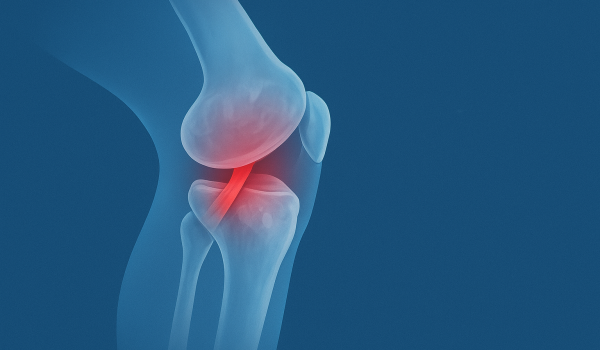

Ligaments connect bones forming joints that allow controlled motion and prevent excessive stretching. Injuries to these structures can occur, especially among active people, athletes, or those who suffer accidents.

- Knee Injuries: Injuries to the anterior cruciate ligament (ACL), posterior cruciate ligament (PCL), medial collateral ligament (MCL), and lateral collateral ligament (LCL) are the most common in sports.